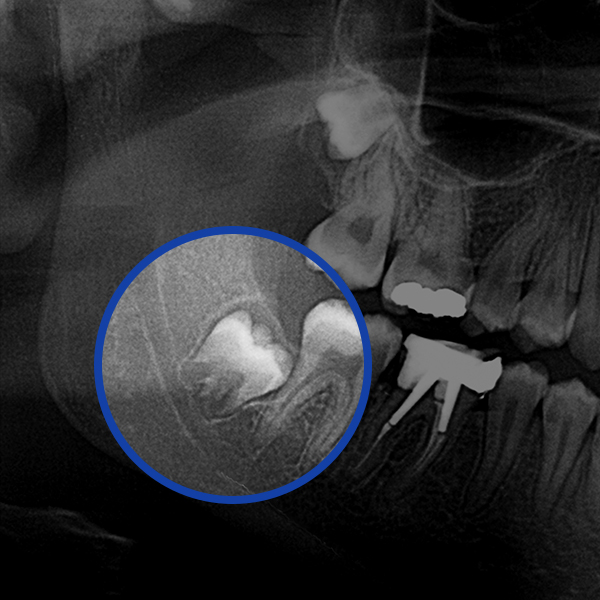

사랑니발치란?

턱뼈의 공간이 부족한 경우, 사랑니가 올바르게 맹출할 수 없습니다.

이런 경우 사랑니가 누워서 맹출되거나 일부만 맹출되면서 여러 가지 문제를 야기할 수 있습니다.

사랑니가 옆으로 누워서 주변치아를 손상시키는 경우

사랑니가 매복되어 있어 잇몸에 염증을 유발하는 경우

관리가 어렵게 맹출되어 충치가 생겼거나 잇몸질환을 유발한 경우

치열에 영향을 주어 부정교합을 유발하는 경우